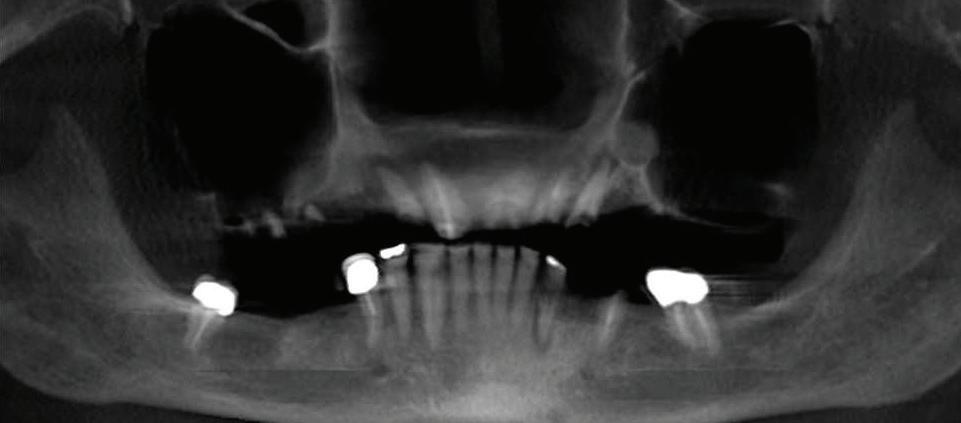

Submitted By Sivakumar Sreenivasan, DMD, MDS Dental Implant Center of Rockville

Can just four implants replace all of the teeth on the top or the bottom of your mouth? Thanks to advances in dental implant technology, that answer is a resounding yes.

Tooth loss is extremely common among adults, especially as we age. Rather than living with the discomfort and hassles of dentures, many people are opting for what is called “all-onfour” dental implant restoration.

An implant is a small titanium

screw that fits inside your jawbone and replaces the root-part of a missing tooth. Minor surgery is required to insert the implants. Once the implant is in place, a crown is attached to give you a highly realistic-looking and functional prosthetic tooth.

You do not need a dental implant for each and every one of your missing teeth. All you need is four precisely placed implants on the top of your mouth, and four on the bottom, to restore your full smile. That’s the beauty of the all-on-four. And because the implant is made of titanium, it has the unique ability to fuse to living bone and function as part of it. So eventually, the dental implant becomes part of the jawbone and serves as a strong, long-lasting foundation for your new teeth.

Besides ensuring that your implants are permanently fixed in place, this bone fusion has another important benefit: it prevents future bone loss in the jaw. This helps to maintain a more